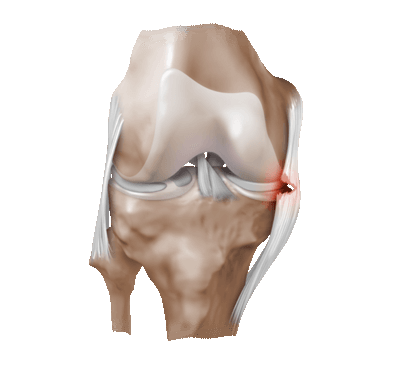

Частичный надрыв боковой связки коленного сустава.

Процедура может быть назначена при:

- неясной причине патологических симптомов, когда другие способы бессильны ее установить;

- разрывах связок, поврежденных сухожилиях;

- подозрении на вывих чашечки (надколенника);

- наличии свободных тел в полости;

- воспалении синовиальной оболочки неопределенного генеза; головки суставной кости;

- травмах, дегенеративно-дистрофических заболеваниях мениска; болезни и гонартрозе;

- внутрисуставных переломах и пр.